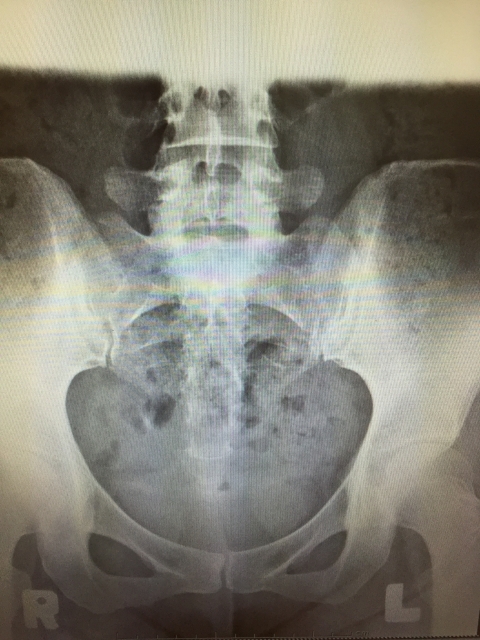

出産時には赤ちゃんの通り道である産道を確保するために、骨盤の前にある恥骨が分離しますし、お尻にある仙骨という骨は後ろ側に大きくせりだします。背骨も出産時には大きく動きます。

・骨盤下口が広がりお尻の形が台形状になっている。

・骨盤の奥行きが広がる。

・腰の反りが少し大きくなる

・股関節は内側にねじれている

・太ももの外側が出っ張っている。

・0脚